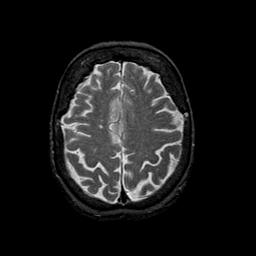

Normal aging, overlay -- Slice #39

[Home][Help][Clinical] Slice 39